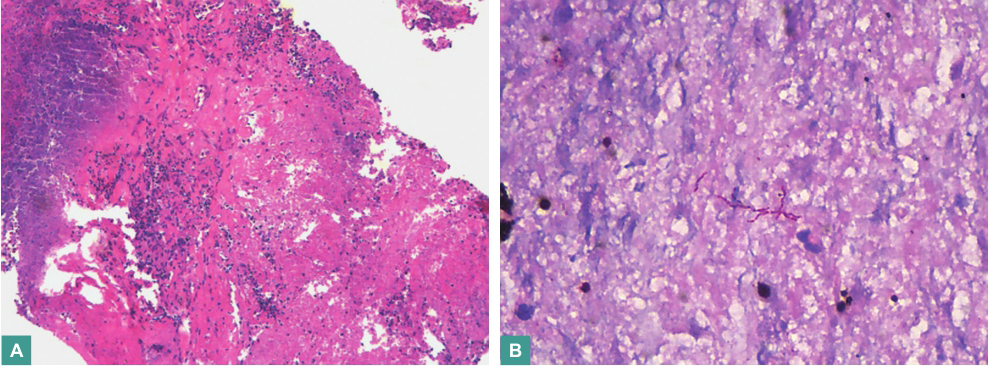

经激素抗炎及抗菌药物抗感染治疗,复查胸部CT提示肺部肿块增大,肿瘤标志物检查均为阴性,2016年3月11日在CT引导下行右肺上叶病灶经皮肺穿刺活检,病理检查镜下见大片坏死,周边伴组织细胞聚集及多核巨细胞反应,间质中见慢性炎症细胞浸润,纤维组织增生(图6),符合肉芽肿性多血管炎改变。

图6 右肺上叶活检病理(HE染色;A.×100;B.×400)